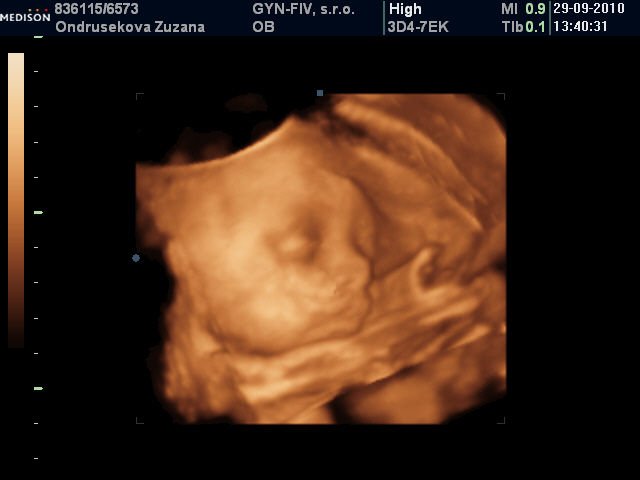

♥70 dní do porodu♥holčička má 1430 g a je hlavičkou dolů♥